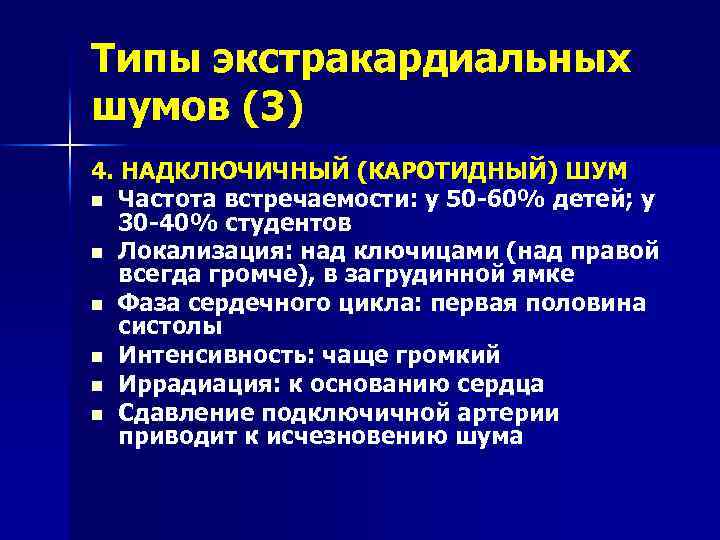

Типы экстракардиальных шумов (3) 4. НАДКЛЮЧИЧНЫЙ (КАРОТИДНЫЙ) ШУМ n Частота встречаемости: у 50 -60% детей; у 30 -40% студентов n Локализация: над ключицами (над правой всегда громче), в загрудинной ямке n Фаза сердечного цикла: первая половина систолы n Интенсивность: чаще громкий n Иррадиация: к основанию сердца n Сдавление подключичной артерии приводит к исчезновению шума